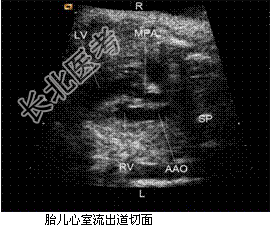

- [材料题] 孕妇,27岁,孕1产0孕25周2d,实验室检查无明显异常。胎儿心脏超声:下腔静脉与形态学右心房连接,肺静脉与形态学左心房连接,其他表现见下图。

(L-左侧,R-右侧,LA-左心房,RA-右心房,LV-左心室,RV-右心室,AAO-升主动脉,MPA-主肺动脉,SP-脊柱)。

- 简答题1、根据上述声像图,该胎儿先天性心脏病最可能为什么?